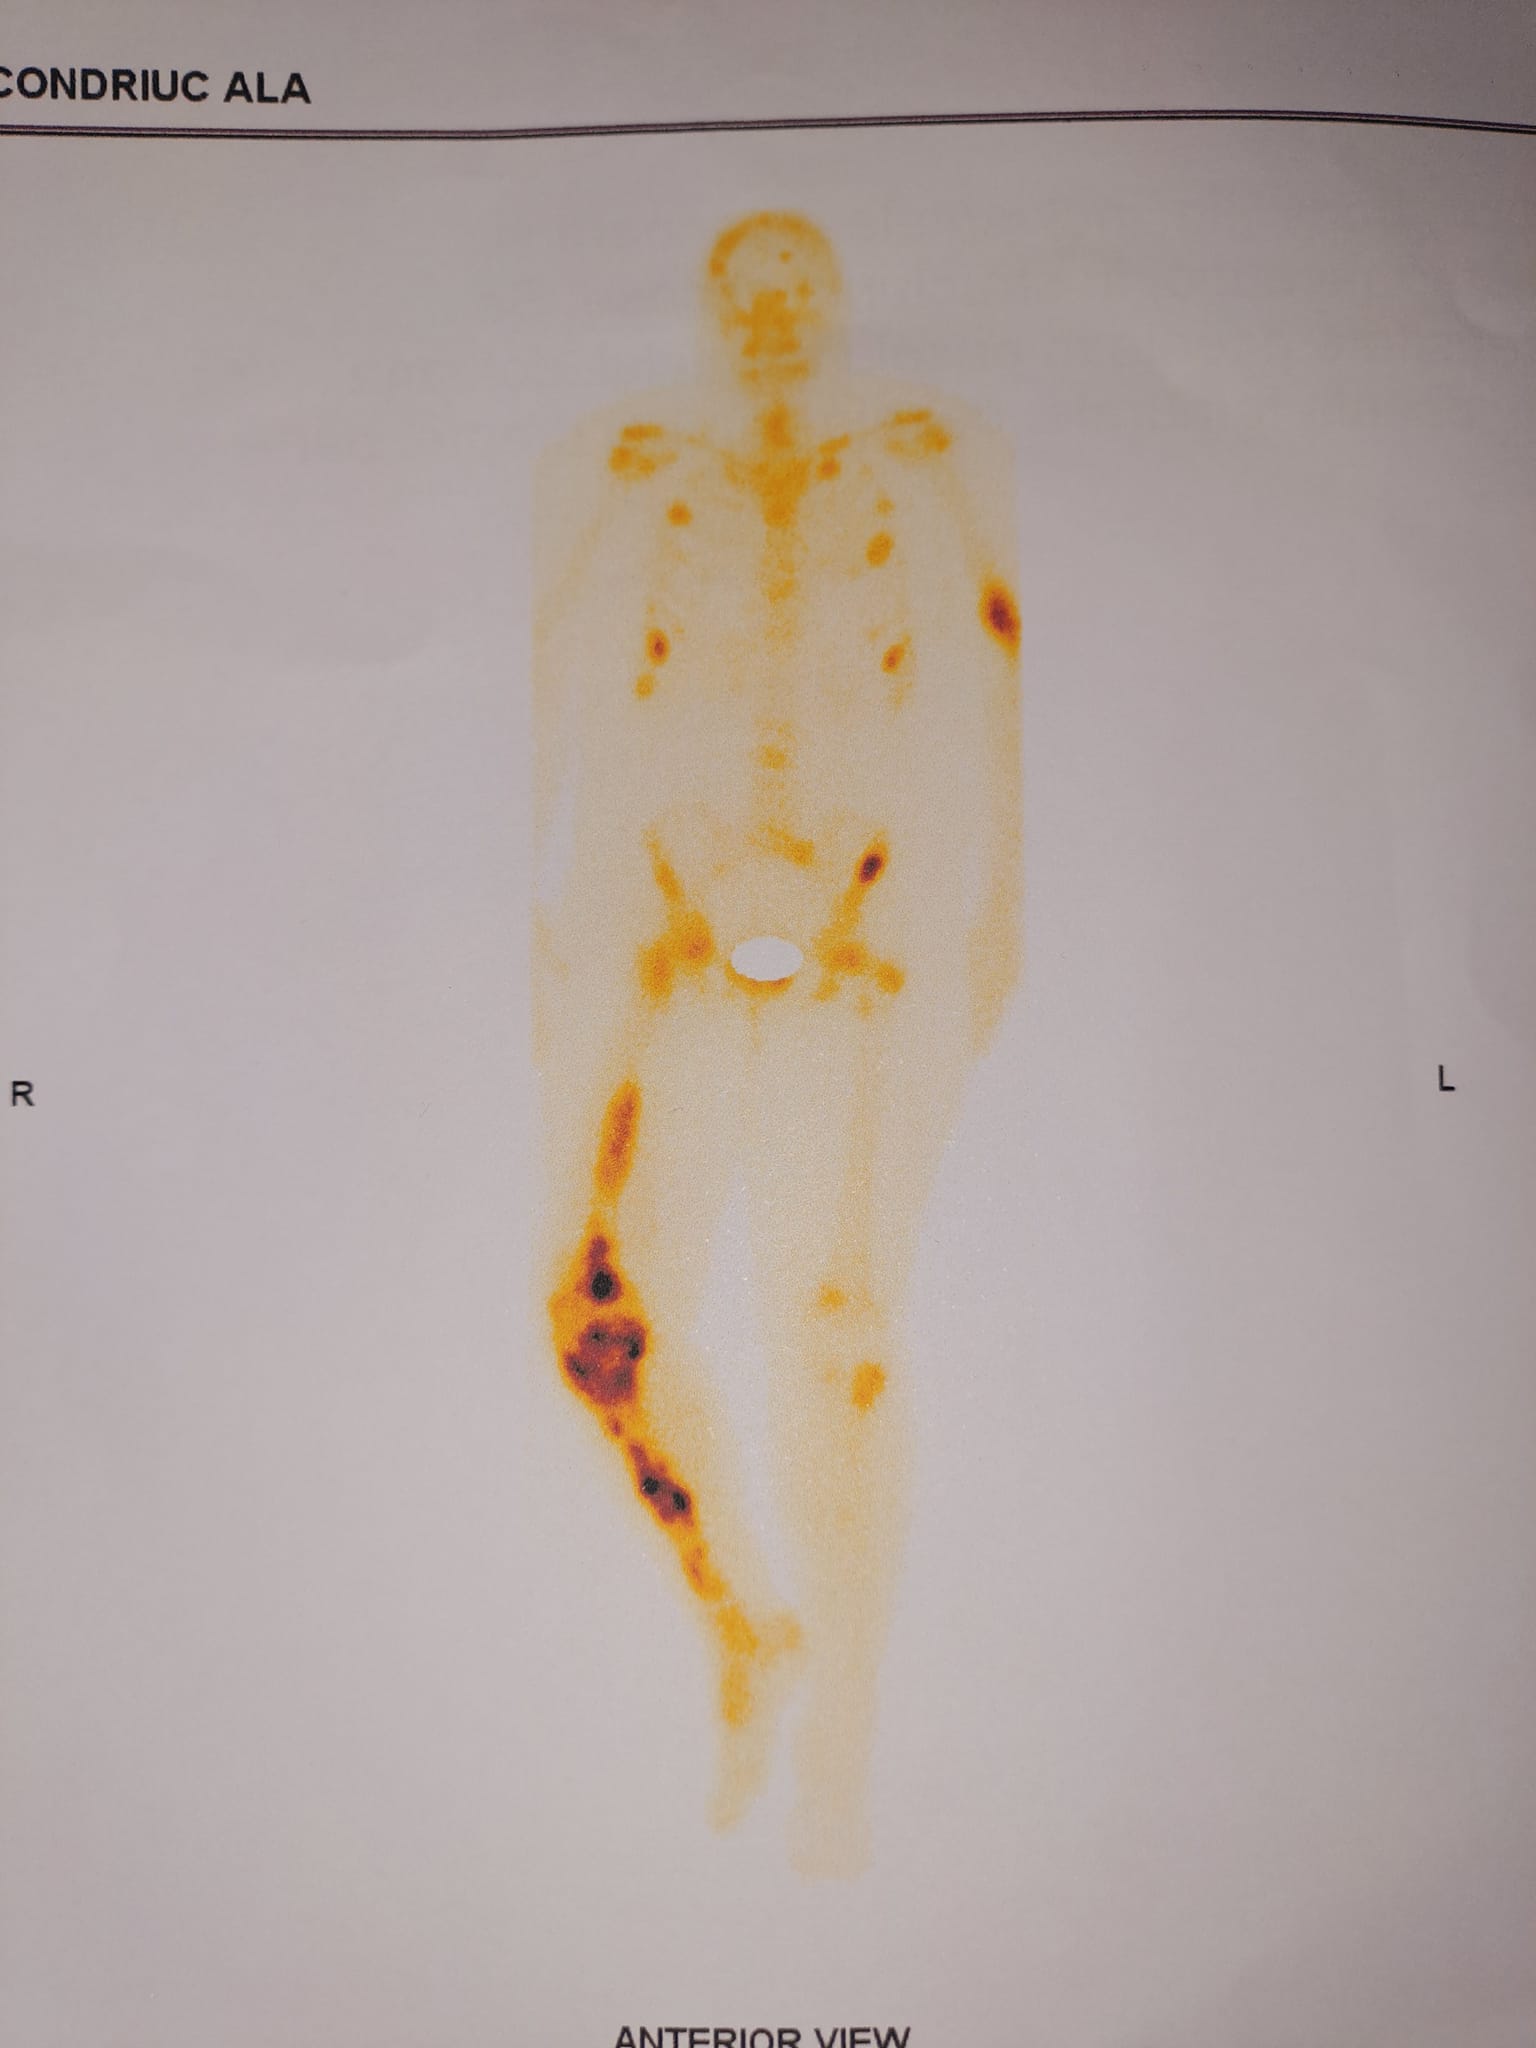

«Мой путь начался с диагноза – рак молочной железы. Тогда я ещё не знала, через какие испытания мне придётся пройти. К сожалению метастазы в костях выявили не сразу, время было потеряно. Теперь мне необходимо дорогостоящее лечение. То есть моя жизнь зависит от денег – осознавать это невыносимо», – делится Алла своими переживаниями.

За последние полгода, болезнь прогрессировала, лишив молодую женщину возможности ходить и обслуживать себя самостоятельно — эти заботы легли на плечи мужа. Он же занимается детьми, пятеро из которых — младше 8 лет.

Кости у Аллы стали очень хрупкими, поэтому несколько месяцев назад у неё случился сложный перелом руки. При операции был повреждён лучевой нерв, и теперь её левая рука практически не действует.

«Так как первую процедуру я перенесла очень тяжело, вторую химию мне ставили частями, несколько дней подряд. Сейчас я уже дома. Химия начала действовать. В тех местах, где метастазы, боль сумасшедшая, не помогают никакие обезболивающие! В первый раз трое суток мучилась. Надо просто пережить этот период, перетерпеть. Я знаю, что должна пройти через это, чтобы стало легче», — рассказывает женщина.